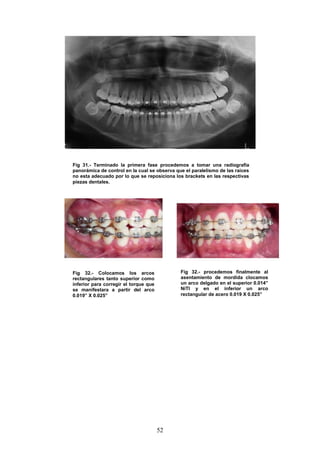

Fig 31.- Terminado la primera fase procedemos a tomar una radiografía

panorámica de control en la cual se observa que el paralelismo de las raíces

no esta adecuado por lo que se reposiciona los brackets en las respectivas

piezas dentales.

Fig 32.- Colocamos los arcos

rectangulares tanto superior como

inferior para corregir el torque que

se manifestara a partir del arco

0.019” X 0.025”

Fig 32.- procedemos finalmente al

asentamiento de mordida clocamos

un arco delgado en el superior 0.014”

NiTI y en el inferior un arco

rectangular de acero 0.019 X 0.025”